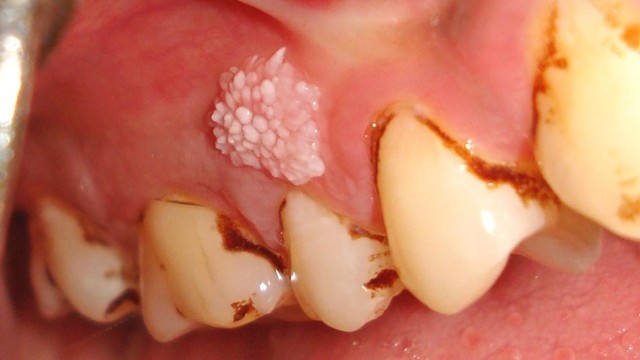

Nướu răng xuất hiện các u nhú, sưng đỏ bất thường nhưng không gây đau có thể là dấu hiệu cảnh báo sùi mào gà ở nướu răng. Việc phát hiện sớm và điều trị đúng cách giúp kiểm soát bệnh và phòng ngừa biến chứng nguy hiểm.